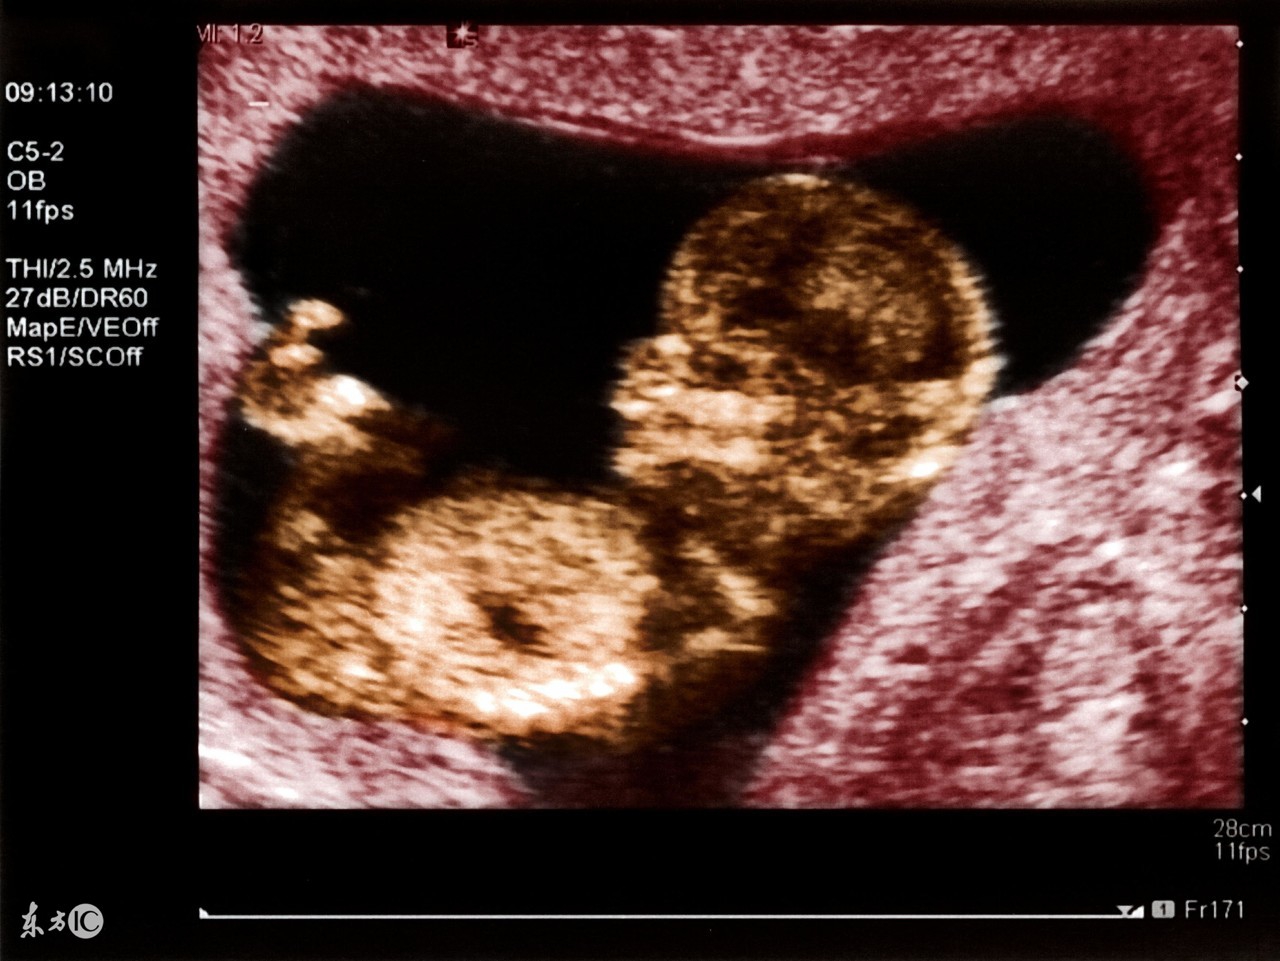

B超对于人体是否安全的关键在于超声的剂量,就是超声的强度和照射时间的乘积。高强度长时间的超声波可对人体或胎儿产生损伤。一般来说,正规B超设备对于超声的输出功率有严格的控制,而且还有医生时刻控制着超声的剂量,在这样的条件下,B超用于妇科检查是安全的。

正常情况下,孕早期应进行一次B超检查,以明确是否宫内妊娠,并确定妊娠的天数。在这里,就来为大家介绍一下如何轻松看懂孕期B超单吧。